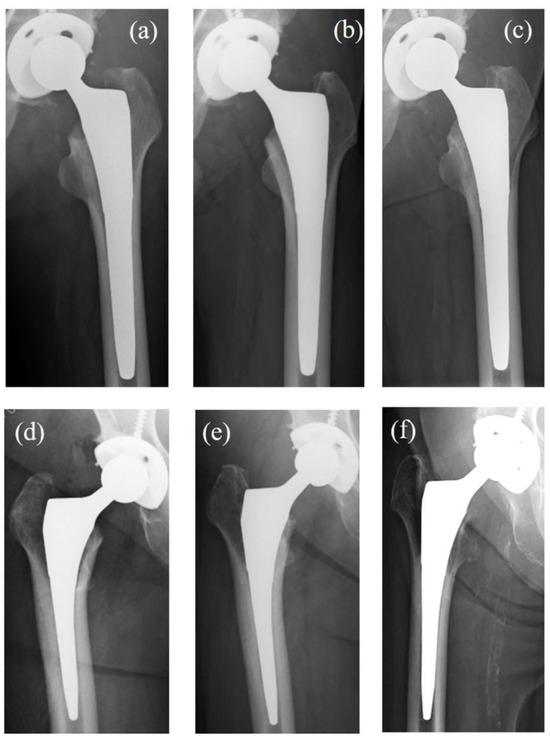

| SS Grade | TNS Group | Control Group | p Value |

|---|---|---|---|

| 0, n (%) | 3 (9) | 0 (0) | 0.03 * |

| 1, n (%) | 9 (27) | 5 (24) | |

| 2, n (%) | 11 (32) | 6 (28) | |

| 3, n (%) | 11 (32) | 5 (24) | |

| 4, n (%) | 0 (0) | 5 (24) |